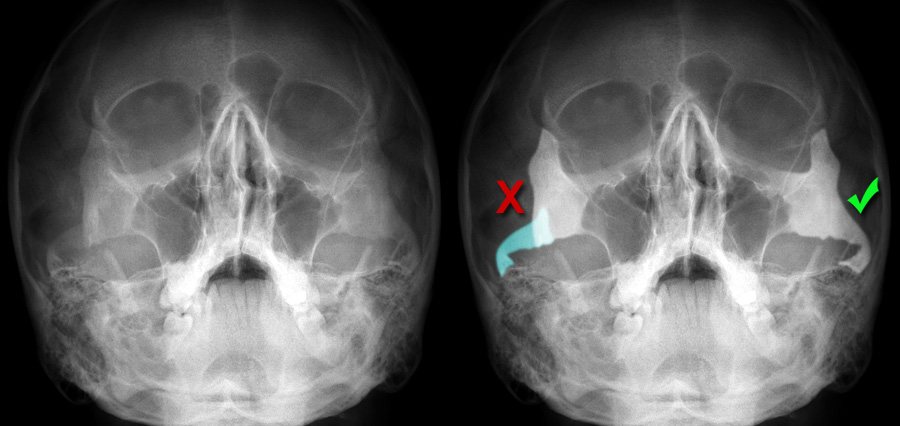

Complex facial fractures

Complex facial fractures 142 photos